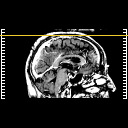

[Home][Help][Clinical] Slice 112

Click on sagittal image to select slice. Click on thin tickmark to change timepoint, or thick tickmark for overlay.